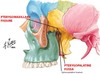

Tiny green area in anterior of skull here:

What bones make it up?

Foramen Caecum

- made up of alae of crista galli (of ethmoid) and frontal bone

- transmits emissary vein from nose to sup. sagittal sinus but is frequently closed

Jugular Foramen

- connects external base of skull to posterior cranial fossa